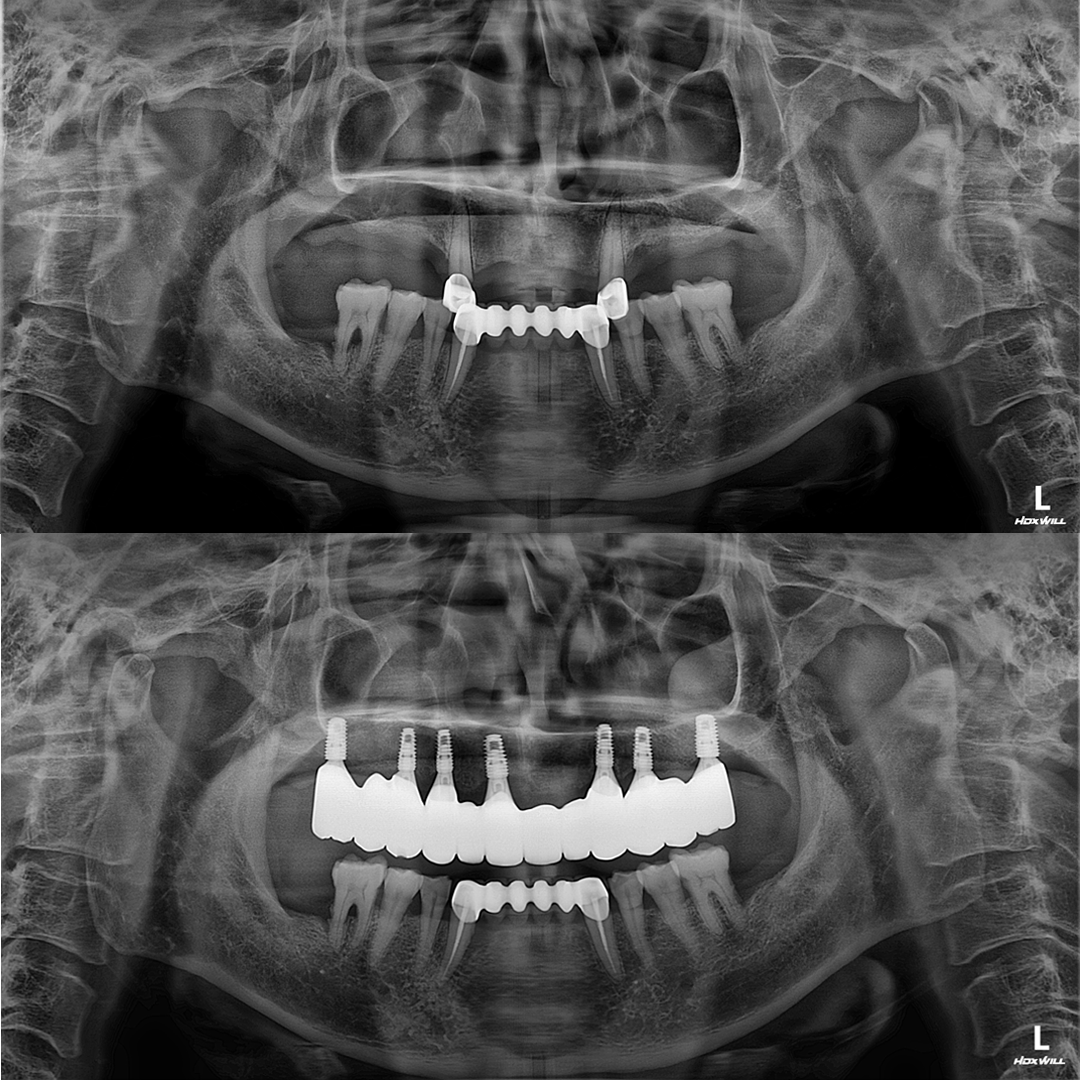

디지털 기술로 더 정확하고 확실하게

디지털(스마트) 임플란트

디지털 스캐닝 기술을 이용해 정교한 3D 모델을 만들고

임플란트의 정확한 위치에 식립하여 높은 정밀도와 맞춤형 치료를 제공합니다.

발치와 임플란트 시술이 단 하루만에!

원데이 임플란트

단 한번의 수술만으로 발치와 동시에

즉시 임플란트를 식립하여 불편감을 줄이고 치료기간을 단축할 수 있습니다.

평균 악당 30분의 빠른 식립시간, 치료 케이스 다수 보유

전체 임플란트

상·하악 전체 치아를 대체하는 임플란트로 최소한의 식립을 통해

자연치아와 비슷한 기능을 수행할 수 있도록 합니다.